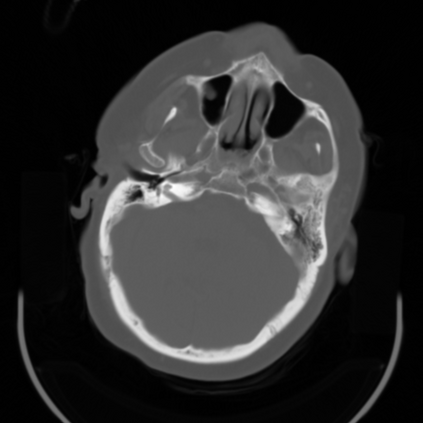

In this work, we present Eformer - Edge enhancement based transformer, a novel architecture that builds an encoder-decoder network using transformer blocks for medical image denoising. Non-overlapping window-based self-attention is used in the transformer block that reduces computational requirements. This work further incorporates learnable Sobel-Feldman operators to enhance edges in the image and propose an effective way to concatenate them in the intermediate layers of our architecture. The experimental analysis is conducted by comparing deterministic learning and residual learning for the task of medical image denoising. To defend the effectiveness of our approach, our model is evaluated on the AAPM-Mayo Clinic Low-Dose CT Grand Challenge Dataset and achieves state-of-the-art performance, $i.e.$, 43.487 PSNR, 0.0067 RMSE, and 0.9861 SSIM. We believe that our work will encourage more research in transformer-based architectures for medical image denoising using residual learning.